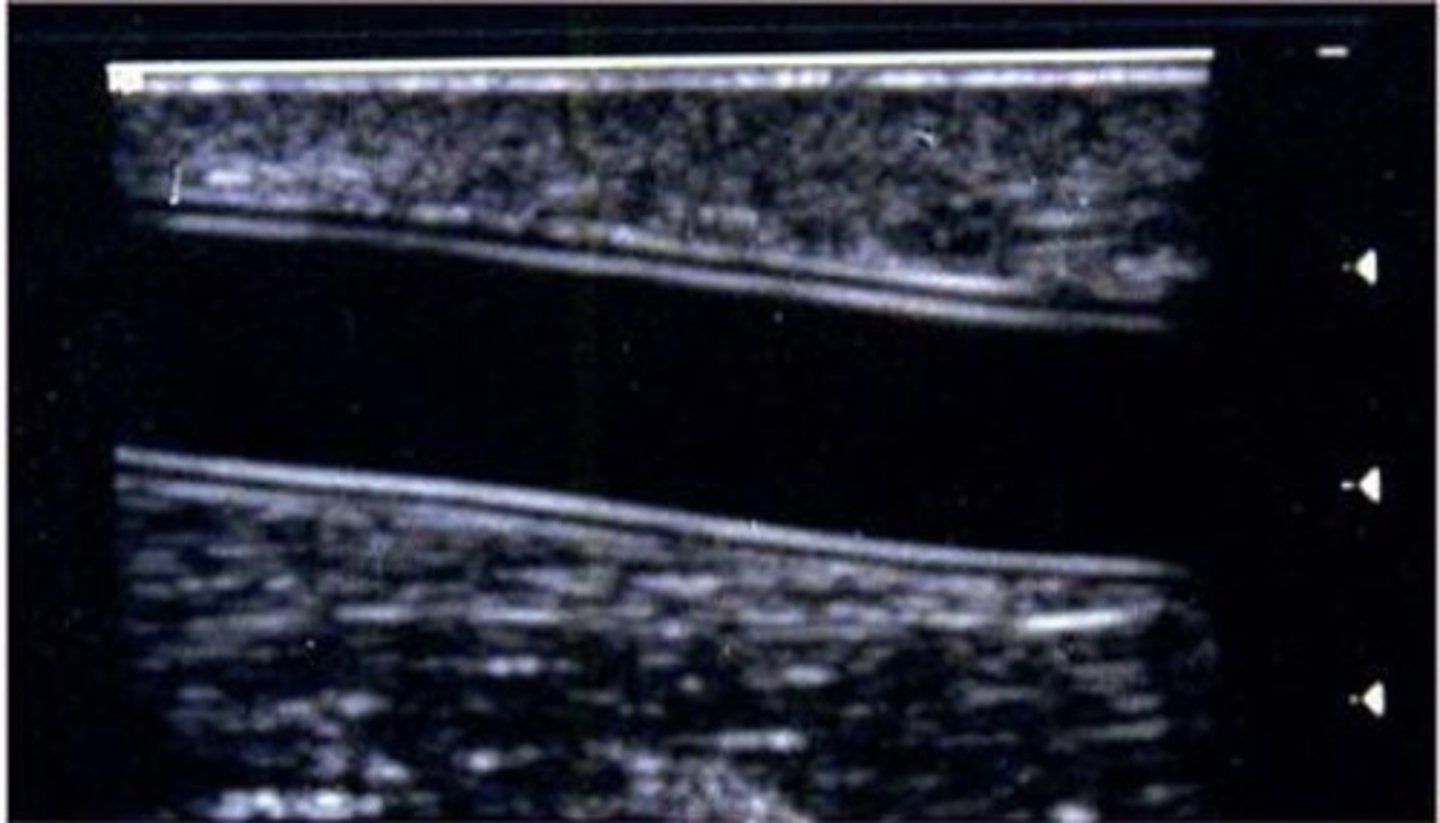

What type of bypass graft is being visualized in the image below?

PTFE